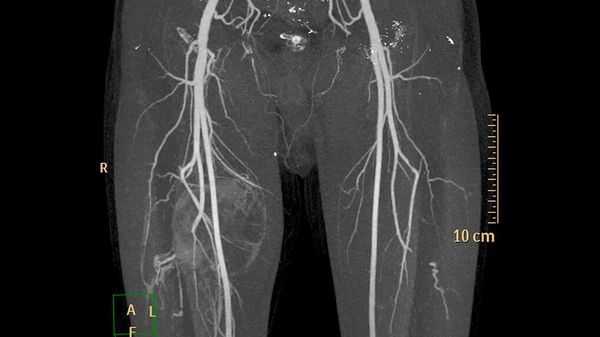

Наиболее важным методом диагностики врожденных артериовенозных свищей является ангиография. Различают прямые и косвенные ангиографические признаки артериовенозных свищей Наличие на ангиограммах контрастированного соустья или сосудистой полости, сообщающейся с артерией и веной, относят к прямым признакам. Косвенно о наличии свища свидетельствуют одновременное контрастирование артерий и вен, расширение просвета приводящей артерии, обеднение сосудистого рисунка дистальнее расположения артериовенозного свища.

Основные методы исследования при аортоартериите Такаясу в клинике диагностики:

- общий анализ крови и на биохимию с целью выявления отклонений в составе крови, характерных для данной патологии; , рентген сосудов путем введения контрастного вещества, помогающего выявить участки сужения артерий;

- рентген грудной клетки для обнаружения пораженных участков в легочной артерии, овальном стволе;

- УЗИ сосудов, метод сканирования для оценки скорости кровотока, состояния коронарных сосудов;